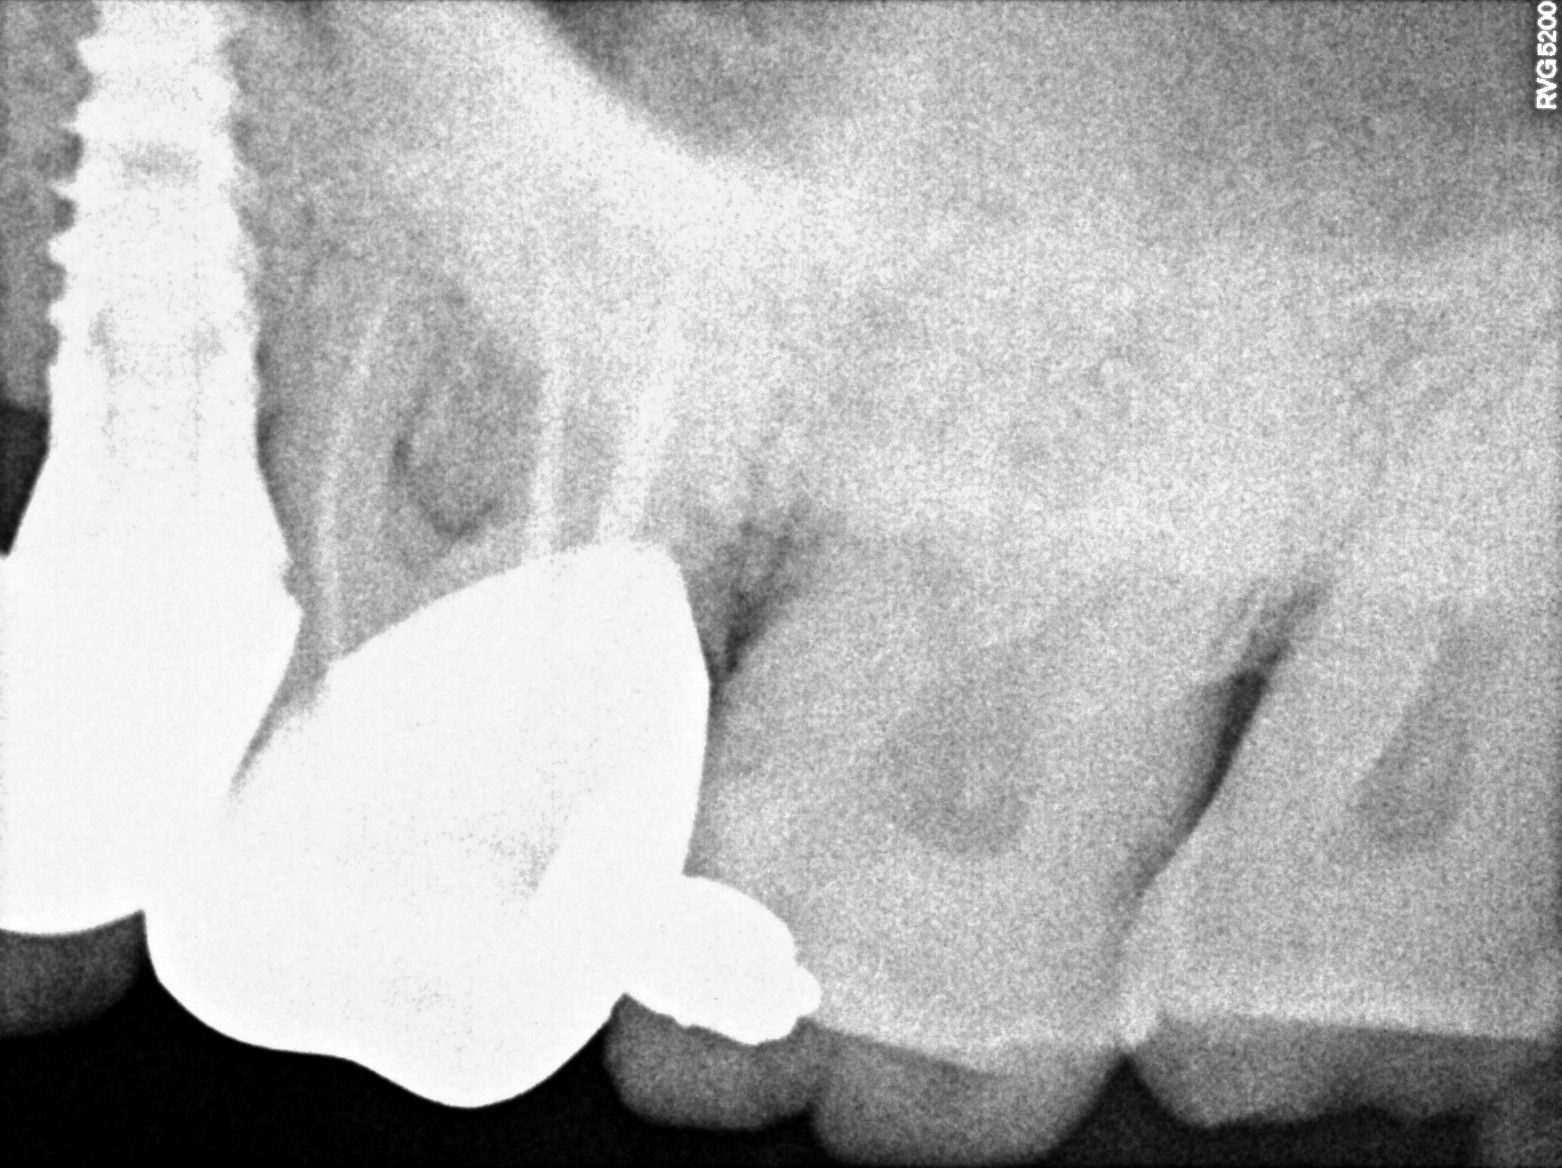

Dental Radiographs FHIR: DocumentReference · LOINC 24641-7

R53 (2).jpg

24641-7